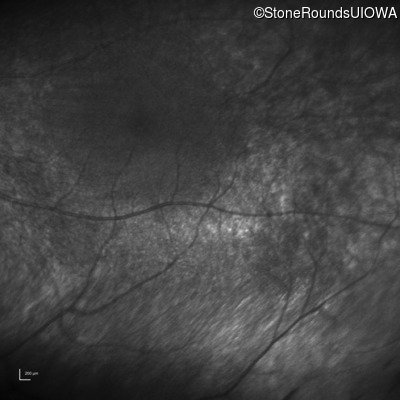

Infrared Fundus Photograph - Right - No Light Perception

Exemplar